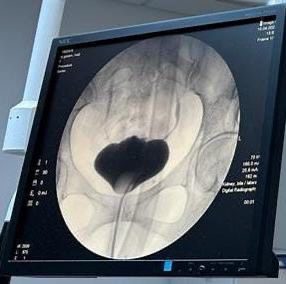

بفضل من الله تمكن الفريق الطبي بقسم جراحة المسالك البولية من إنهاء معاناة سيدة بالعقد الرابع، دامت لأكثر من ٤ سنوات، حيث كانت المريضة تعاني من ناسور ما بين المثانة والمهبل نتيجة مضاعفات ولادة قيصرية قبل خمس سنوات.

المرحلة الأولى تمت ولله الحمد بعمل إزالة للناسور وترميم المنطقة ما بين المثانة والمهبل وقد تكللت بالنجاح، والمرحلة الثانية تمت بعد الأولى بستة أشهر وذلك بزيادة حجم المثانة عن طريق أخذ جزء من الأمعاء الدقيقة وعمل رقعة للمثانة.

وأوضح الدكتور حاتم النصيان (رئيس الفريق الطبي) إن التحدي الذي كان يواجه الفريق الطبي يكمن في مشكلتين وهي الالتصاقات الشديدة بمكان العملية كذلك حجم المثانة الصغير جدا وذلك بسبب تعدد العمليات السابقة بالمثانة.